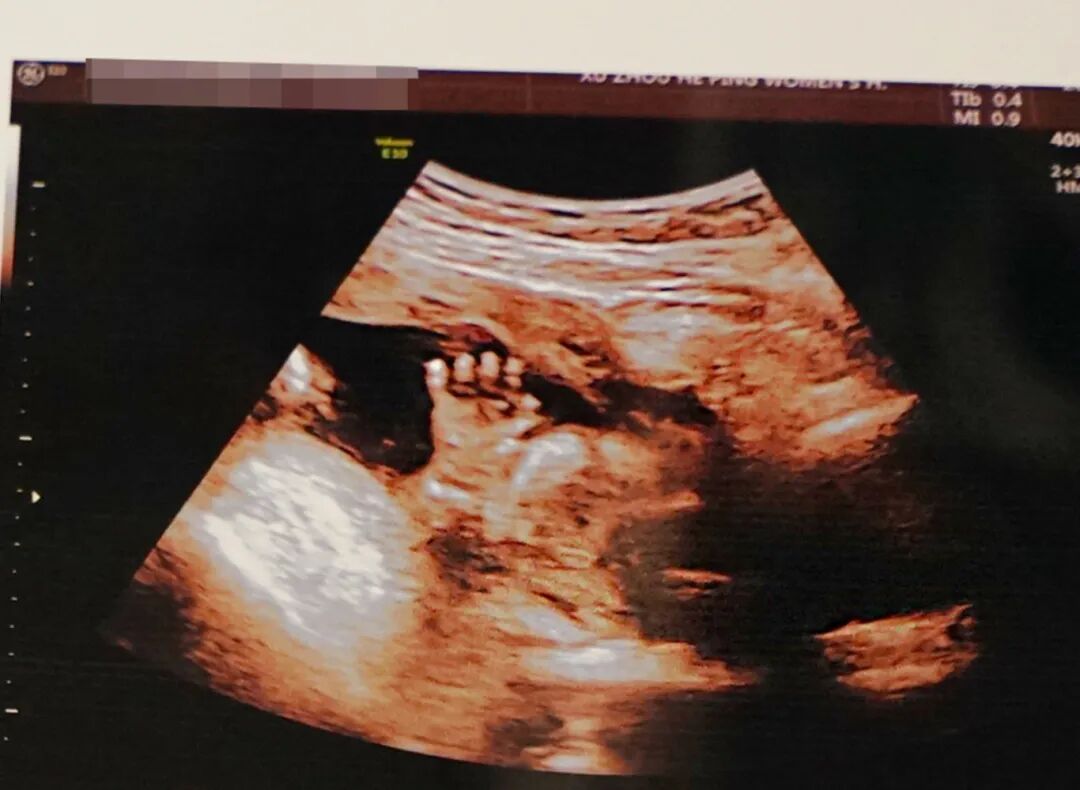

邱博士高清超声成像精彩画面(滑动查看更多)

疑难复杂情况胎儿影像(滑动查看更多)